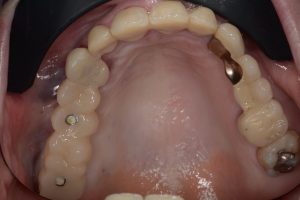

A restauração provisória de longo prazo, uma ponte fresada de cinco unidades feita de resina de alto desempenho com base em PMMA, foi primeiramente verificada quanto ao ajuste e foi fixada aos implantes sem a necessidade de ajustes individuais (Fig. 14). A precisão do fluxo de trabalho digital foi refletida no ajuste exato da restauração provisória.

Em sua quarta visita ao consultório, cerca de cinco meses após a cirurgia, a paciente recebeu a ponte permanente. Ela estava muito satisfeita com seus novos dentes, tanto do ponto de vista estético quanto funcional. As restaurações protéticas de zircônio combinam harmoniosamente com a dentição natural restante da arcada superior da paciente (Fig. 16). A paciente ficou particularmente satisfeita com o procedimento minimamente invasivo, pois não sentiu dor nem inchaço em nenhum estágio do tratamento.